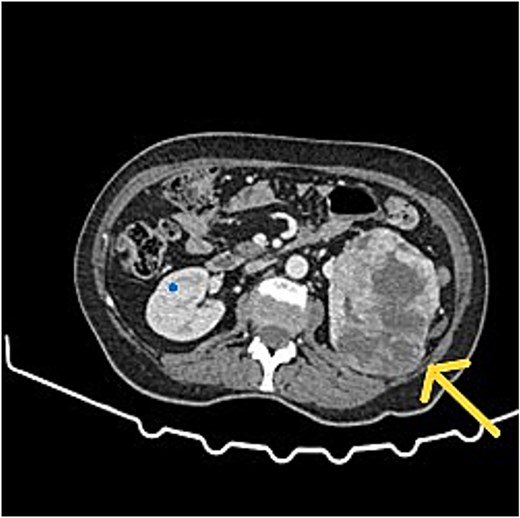

Patients referred with peritoneal malignancy were evaluated in a speciality multidisciplinary team (MDT) meeting with scans reviewed by specialist peritoneal malignancy radiologists (Figs 1 and 2) and experienced peritoneal malignancy surgeons. The standard imaging was dual contrast computed tomography (CT) of the chest, abdomen and pelvis. Tumour marker assessments include CEA, CA19.9, and CA 125. Patients with a renal mass were discussed in a renal cancer MDT.

CT scan showed left RCC, appendix tumour with surrounding mucin.